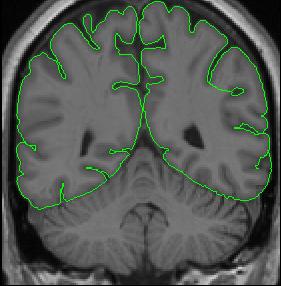

Segmentation: Exteriors

Cerebral Exterior

General Description

The cerebral exterior is the border between the subarachnoid CSF and neural tissue (e.g. the first layer of cortical neurons), and should correspond to the pia mater. Thus, the cerebral exterior separates brain from non-brain, cerebrum from cerebellum, and divides the brain in to its two hemispheres. Your outlines should not include anything that is not brain (e.g. dura mater, other meninges, etc.). For our purposes, optic chiasm is considered to be outside of the brain, and therefore excluded from exterior outlines. To determine what is and what isn't brain, it is useful to check the other two views (sagittal and axial). Once you've determined what is and isn't brain, use the draw tool to make the appropriate corrections on your exterior outline.